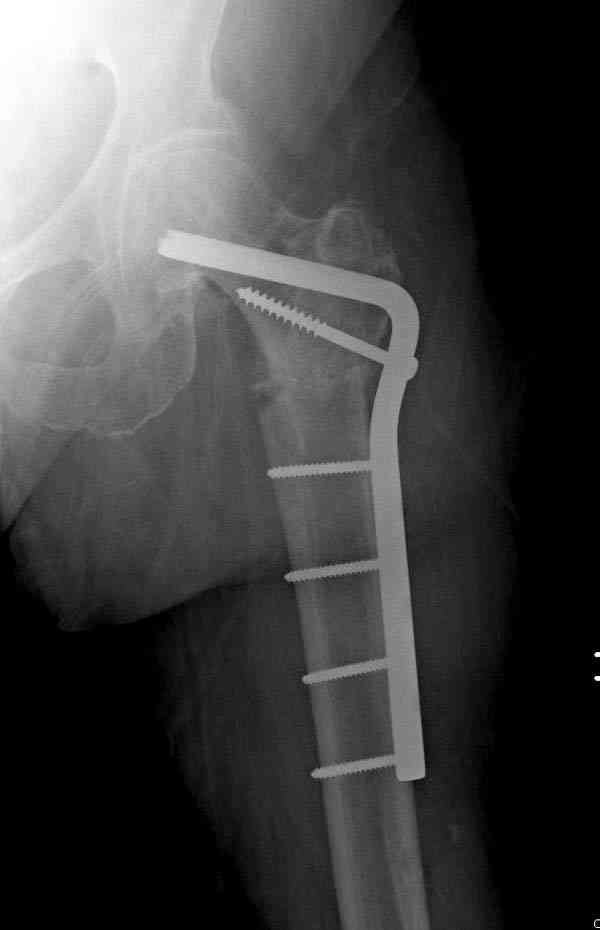

77 летняя больная направлена в нашу клинику на дальнейшее лечение. Из истории, травму получила в сентябре 2007 года и по поводу перелома шейки бедра больная была проперирована тремя каннюлированными шурупами с явным нарушением технологии установки шурупов. Внизу вместо одного шурупа имеется два, что привело к стрессу латерального кортекса. Через месяц по поводу ятрогенного подвертельного перелома сделана фиксация длинной Гамма 3. Установлен без проксимальной блокировки? (set screw). В данный момент имеется несостоятельность конструкции и ложный сустав. Передвигается с помошью костылей, конечность укорочена на 2 см. Какие будут рекомендации?Djoldas Kuldjanov, MDDepartment of Orthopedic SurgerySt. Louis University Medical Center

Не стали усложнять интрамедуллярным вариантом коррекции, легче контролировать коррекцию пластиной, поэтому сделали операцию 95 градусной Blade Plate, разогнув до 110 градусов.

Надеемся на успех, потому что до введения пластины дефект от импланта забили костной стружкой и удалось создать компрессию между отломками, максимальную для импланта (150 кило/паунд). Сделана дополнительная костная пластика и за счет измененного угла пластины устранено укорочение конечности.